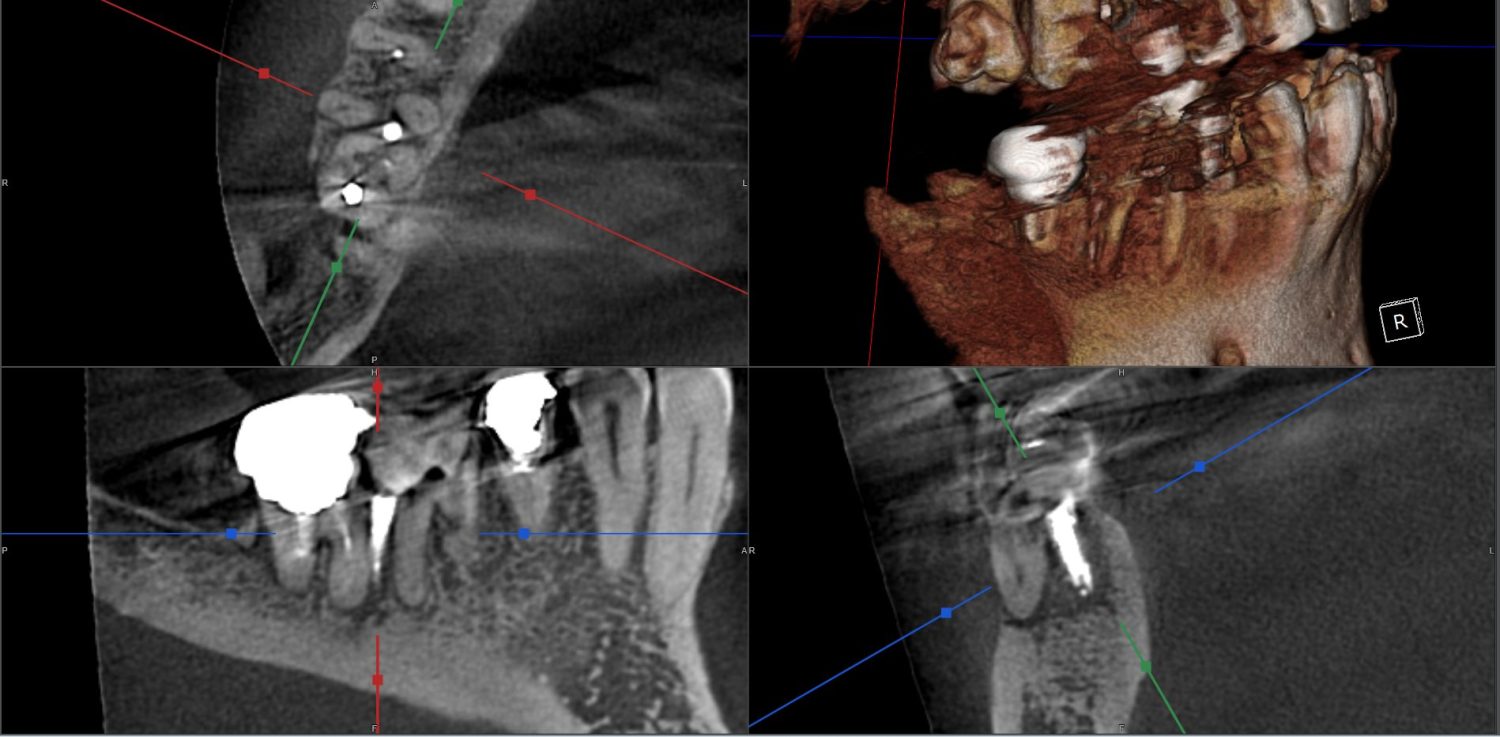

| 主訴 | 過去の治療にて根管充填後、噛むと違和感・痛みが出てきた。一度詰めた薬を撤去してもらったが症状が変わらなかったため来院。 |

| 治療内容 | ラバーダム防湿を行い、マイクロスコープにて根尖部の溢出ガッタパーチャの除去を行いました。 |

| 想定されたリスク | ガッタパーチャが取り切れない可能性がある。除去したとしても違和感・痛みが続くこともある。 ガッタパーチャを取ることにより根尖が過拡大されてしまい、根管充填時に更なる溢出を起こす可能性がある。 MTAセメント根充や外科的な処置が必要となる可能性がある。 |

CT撮影により根尖部にガッタパーチャの溢出を確認。

拡大視野下にて残存ガッタパーチャを確認しながら過拡大に注意しながら除去。

その後根管充填を行った症例です。ガッタパーチャ除去したことで症状が改善されました。